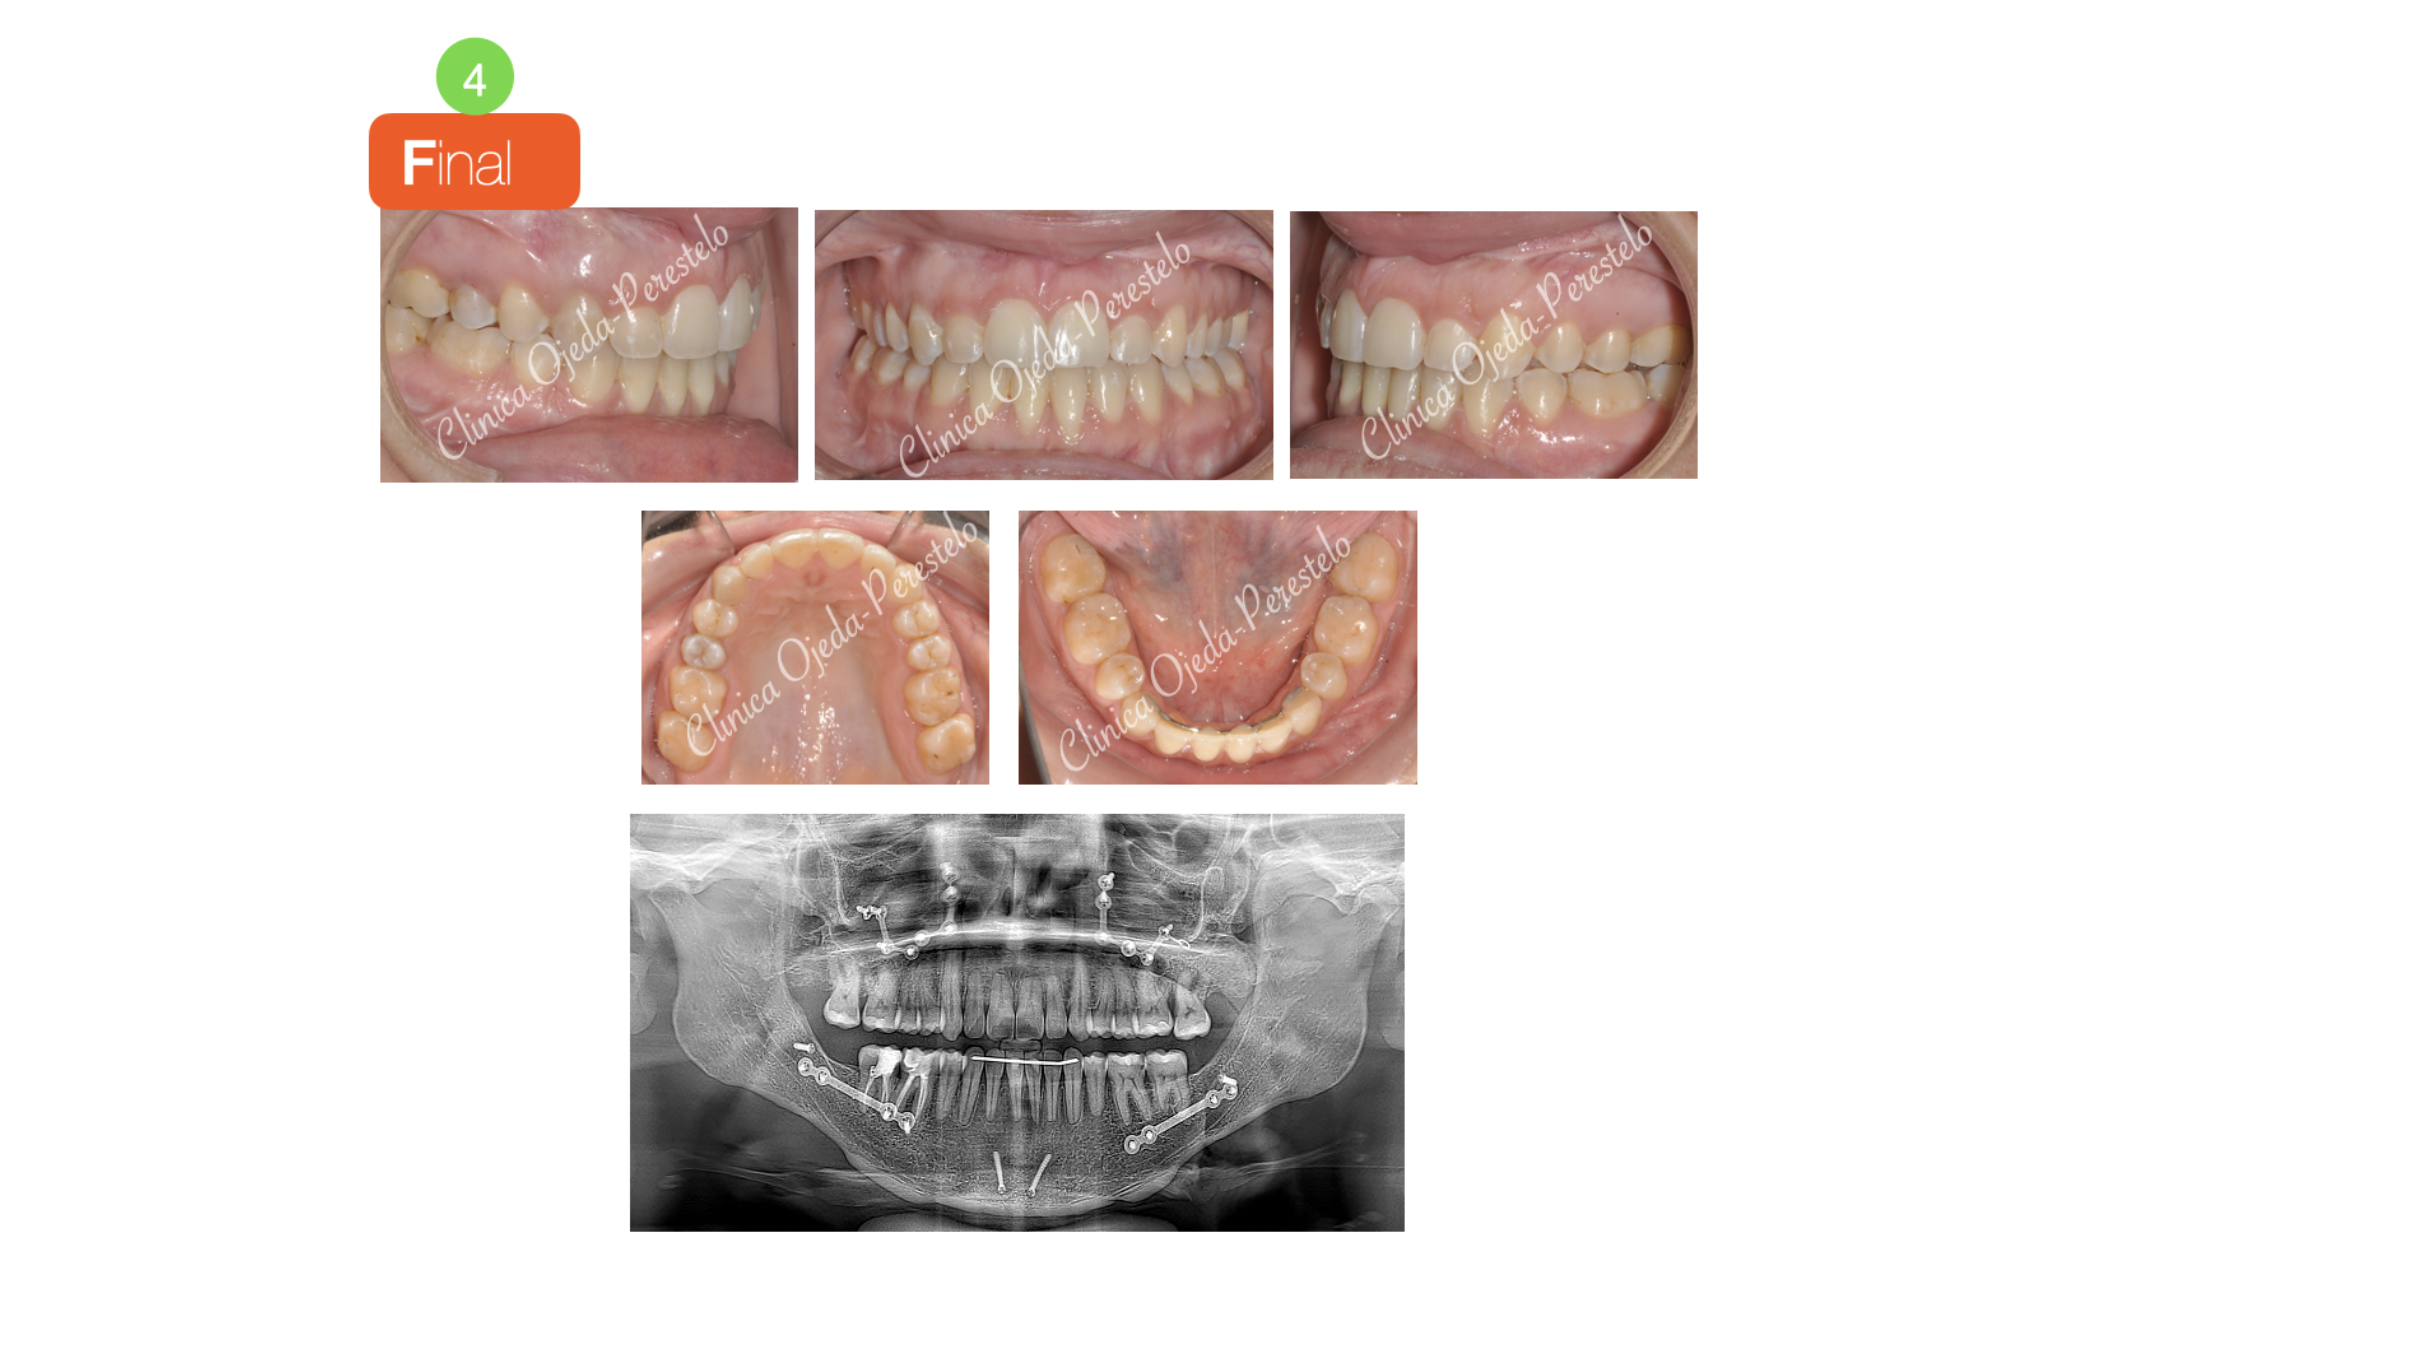

Se decide realizar, previo a la intervención, un centrado de los incisivos sobre sus bases óseas (descompensación dentaria) siendo necesario para ello la extracción de dos premolares inferiores (Sistema Damon).

Una vez están las arcadas alineadas y ordenadas se planifica por el equipo del Dr Hdez-Alfaro un Lefort con Avance y giro Antihorario del Maxilar conjuntamente con Osteotomia Sagital de Rama de Avance Mandibular con Mentoplastia.

Quisiera destacar la mejoría alcanzada a nivel facial, dentario y sobre todo en la calidad del sueño de la paciente.